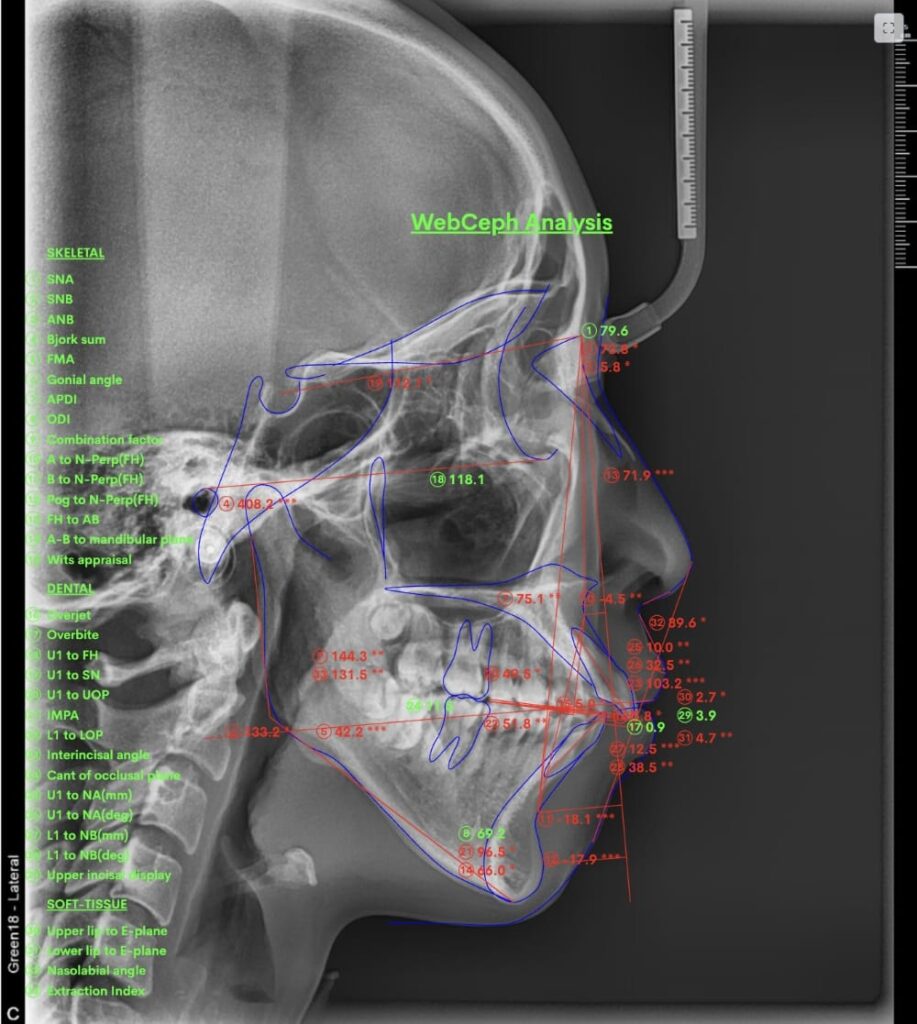

また、歯列と骨格の両方が影響しているケースも少なくありません。そのため、「矯正だけでどこまで下がるのか」を正確に判断するには、セファロ分析(横顔のレントゲン)や噛み合わせの評価が欠かせません。

② セファロ(横顔レントゲン)分析

骨格的な問題があるかどうかを数値で評価します。

上顎・下顎の前後関係、前歯の傾斜角度、口元の軟組織のバランスなどを客観的に確認することで、「歯が原因なのか」「骨格が原因なのか」を明確にします。

- セファロによる骨格診断